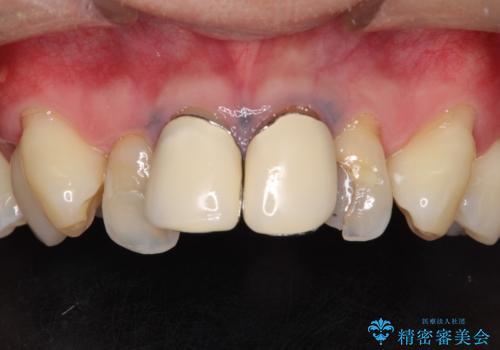

- 上の前歯の見た目が気になるとのことで来院されました。

上の前歯の4本が神経の処置がされており、前から2番目の歯が内側に入り込んでしまっていました。

また、金属で治療された根本の歯茎が黒く変色(メタルタトゥー)しており、余計に見た目がよくない状態となっておりました。

矯正治療で前歯の歯並びを整えてからセラミックほ装着する計画としました。